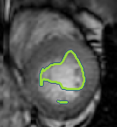

4.2 Visual assessment

We select the case that achieves the highest and lowest dice score for visual assessment. Fig. 4 shows example segmentation results where the proposed method achieved the highest agreement with the ground truth delineations. Fig. 5 shows example segmentation results where the proposed method achieved the lowest agreement with the ground truth delineations.